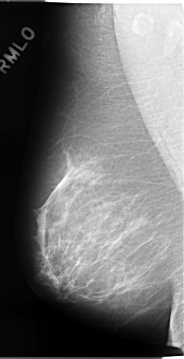

C_0075_1.RIGHT_MLO

DATE_OF_STUDY 10 1 1994

PATIENT_AGE 51

FILM_TYPE REGULAR

DENSITY 2

RIGHT_CC LINES 4648 PIXELS_PER_LINE 2472 BITS_PER_PIXEL 12 RESOLUTION 50 NON_OVERLAY

RIGHT_MLO LINES 4664 PIXELS_PER_LINE 2392 BITS_PER_PIXEL 12 RESOLUTION 50 NON_OVERLAY